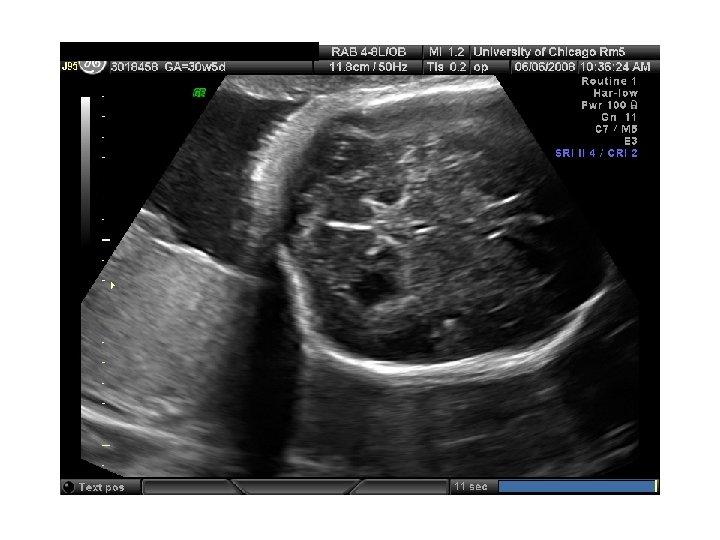

QUIZ What is Your Diagnosis? Case: Patient J. F. 30 years old, at 32 week gestation. Presented with the following pictures.

Answer: a) Trisomy 21 b) Non-immune Hydops c) Paravo virus Infection